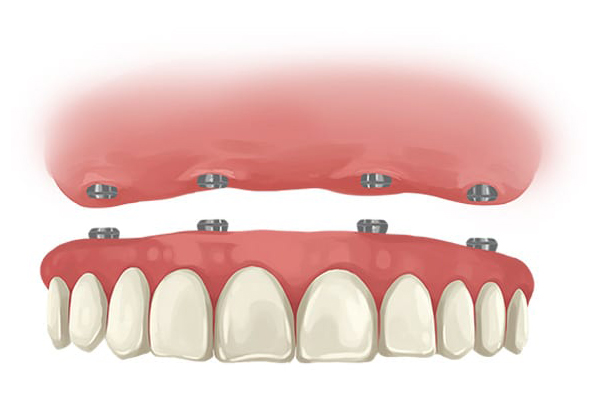

All-On-4 Dental Implants are a revolutionary full-mouth rehabilitation solution that replaces a full set of teeth using only four implants. The unique feature of this treatment method is that it utilizes a reduced number of implants, strategically placed at specific angles, to provide maximum stability and support for a full-arch prosthesis.

The procedure involves placing two anterior straight implants and two posterior implants angled up to 45 degrees. This arrangement leverages the available bone structure, particularly useful in patients with significant bone loss, eliminating the need for bone grafting or sinus lifts. The prosthetic teeth are then attached to these implants, providing a fully functional set of teeth.

The All-On-4 technique is highly effective and offers several benefits, including immediate functionality, improved aesthetics, and increased comfort. It's particularly suited for patients who have lost most or all of their teeth and are looking for a fixed, long-term replacement solution that mimics the look and function of natural teeth.

The treatment is usually completed in a single day, hence it's also known as "Teeth in a Day" or "Same Day Teeth".